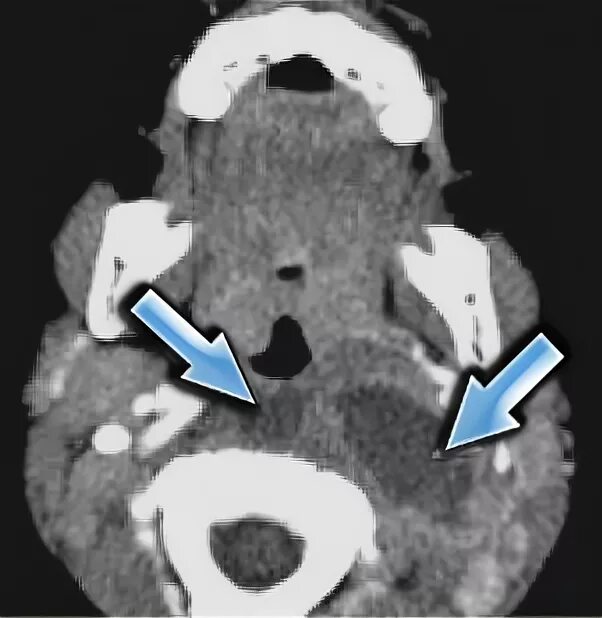

Кт тканей